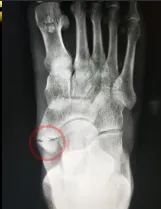

覃阿姨因右足背疼痛而受困扰多年,疼痛部位可摸及硬骨。因担心自己就医会检查出“骨癌”而迟迟不肯就医,近期因迷恋上广场舞,每次舞蹈结束后疼痛明显加重,穿鞋时也因摩擦加重疼痛而不得来院就诊。入院后,完善足部DR检查,可发现,她比别人多了一块骨头——副舟骨。

通过DR检查,我们可看到覃阿姨的足副舟骨的分型是属于2型的。因近期才通过口服非甾体类药物,并嘱咐注意日常生活习惯,日常更换宽松的休闲鞋,结合中医、康复治疗后,疼痛得到显著改善。